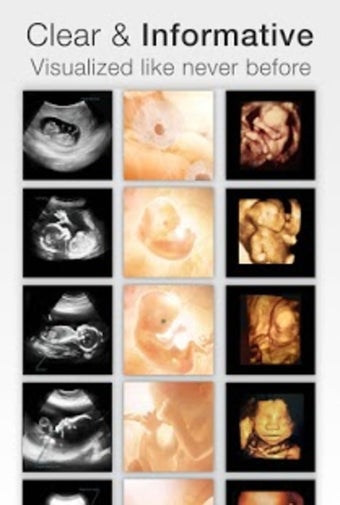

아기의 발달과 진행 상황을 추적하고 손끝에서 올바른 정보를 얻을 수 있는 좋은 방법입니다.